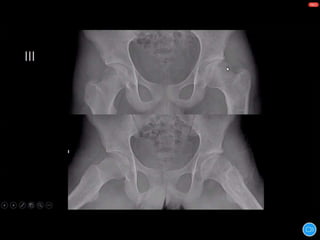

WALDENSTROM STAGES:

1) INITIAL STAGE

2) FRAGMENTATION STAGE

3) REOSSIFICATION STAGE

4) HEALED STAGE